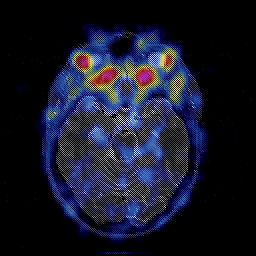

Glioblastoma multiforme overlay -- Slice #21

[Home][Help][Clinical][Tour 1][Tour 2][Tour 3] Slice 21